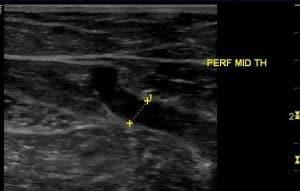

This course provides a comprehensive guide to the ultrasound techniques used for assessing the superficial venous system, crucial for procedures such as bypass grafting and hemodialysis access fistula creation. Learn how to evaluate veins like the great and small saphenous veins, as well as the cephalic and basilic veins, by mapping their course, diameter, and patency. Key topics include the identification of normal venous structures, common anatomical variations, and potential issues such as thrombus, varicosities, and calcifications. This course is ideal for clinicians performing pre-operative venous assessments for surgical procedures.

Describe the basic techniques of venous mapping

Describe diagnostic ultrasound criteria utilized in venous mapping